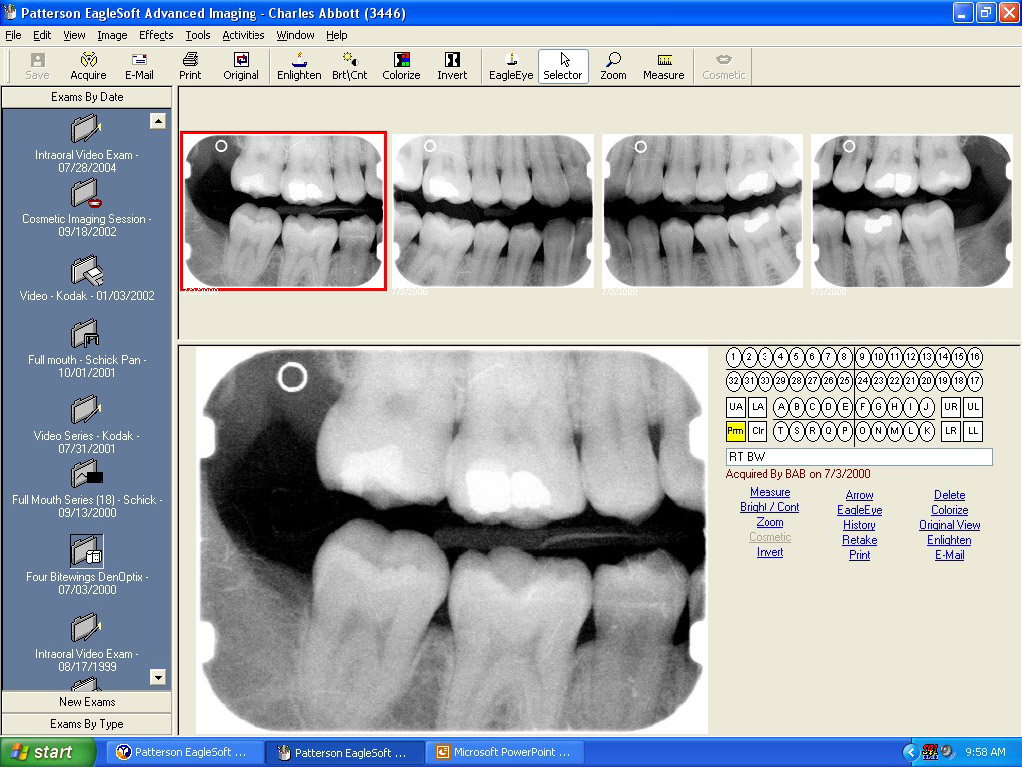

Figure 2. Photostimulable phosphor plates are another type of digital receptor. (Air Techniques, Inc)

Figure 2

Indirect Receptors—Photostimulable phosphor plates (PSP), also known as storage phosphor plates (SPP), uses indirect receptors. PSP/SPP are flexible, wireless receptors that are similar in size and thickness to film (Figure 2). Phosphor plates are available in the same sizes as intraoral film including 0, 1, 2, 3, and 4. An individual plate must be used for each projection in the survey, just like film. The phosphor plates consist of a polyester base that is coated with a crystalline halide emulsion of a europium-activated barium fluorohalide compound.19 When x-rays interact with the phosphor, a latent image is formed and stored until the energy is released during a scanning process.